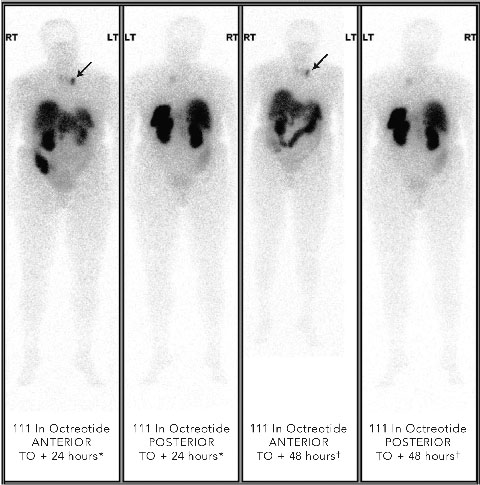

Localisation studies with a 123 I-metaiodobenzylguanidine scan identified increased tracer uptake within both the left adrenal region and left anterior mediastinum. Computed tomography and magnetic resonance imaging (MRI) scans showed large bilateral renal angiomyolipomas (AMLs), a right renal artery aneurysm, a bulky left adrenal gland with no discrete mass lesion, and a 15 mm calcified lesion within the left anterior mediastinum (not related to the sympathetic chain). Results of a positron emission tomography scan were negative. However, an octreotide scan showed mild tracer uptake in the left adrenal region and marked focal uptake within the left anterior mediastinum (Box 2).

It was felt unlikely that the left adrenal gland image represented a phaeochromocytoma and likely that the mediastinal lesion was a phaeo-chromocytoma lymph node metastasis. After the addition of atenolol 100 mg daily to the patient’s drug regimen, the left anterior mediastinal lesion was excised via a cervical approach without complication. Histological examination confirmed a phaeochromo-cytoma metastasis within a lymph node. After the operation, blood pressure improved significantly. Plasma metanephrine levels have remained normal for over a year.